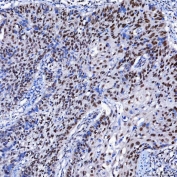

IHC staining of FFPE human ovarian serous cancer tissue with SF3a120 antibody. HIER: boil tissue sections in pH8 EDTA for 20 min and allow to cool before testing.